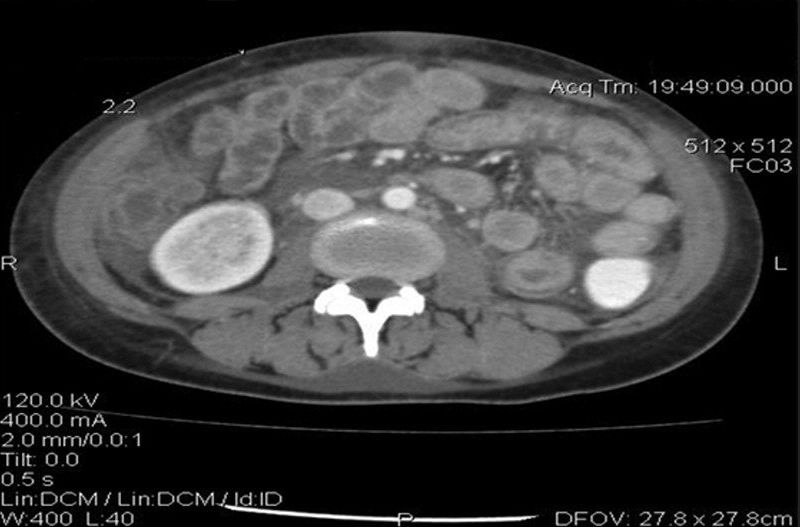

癌胚抗原(CEA)水平正常,但CA-125水平升高为93.5μg/ml(正常范围,0~35μg/ml)。进行腹部和盆腔的CT扫描,证实存在中度腹水和腹膜结节(图2)。膀胱壁和肠壁增厚(图3)。双侧肾积水和多个扩大的主动脉旁淋巴结也可见(图4)。

图3 腹部增强CT显示肠袢增厚